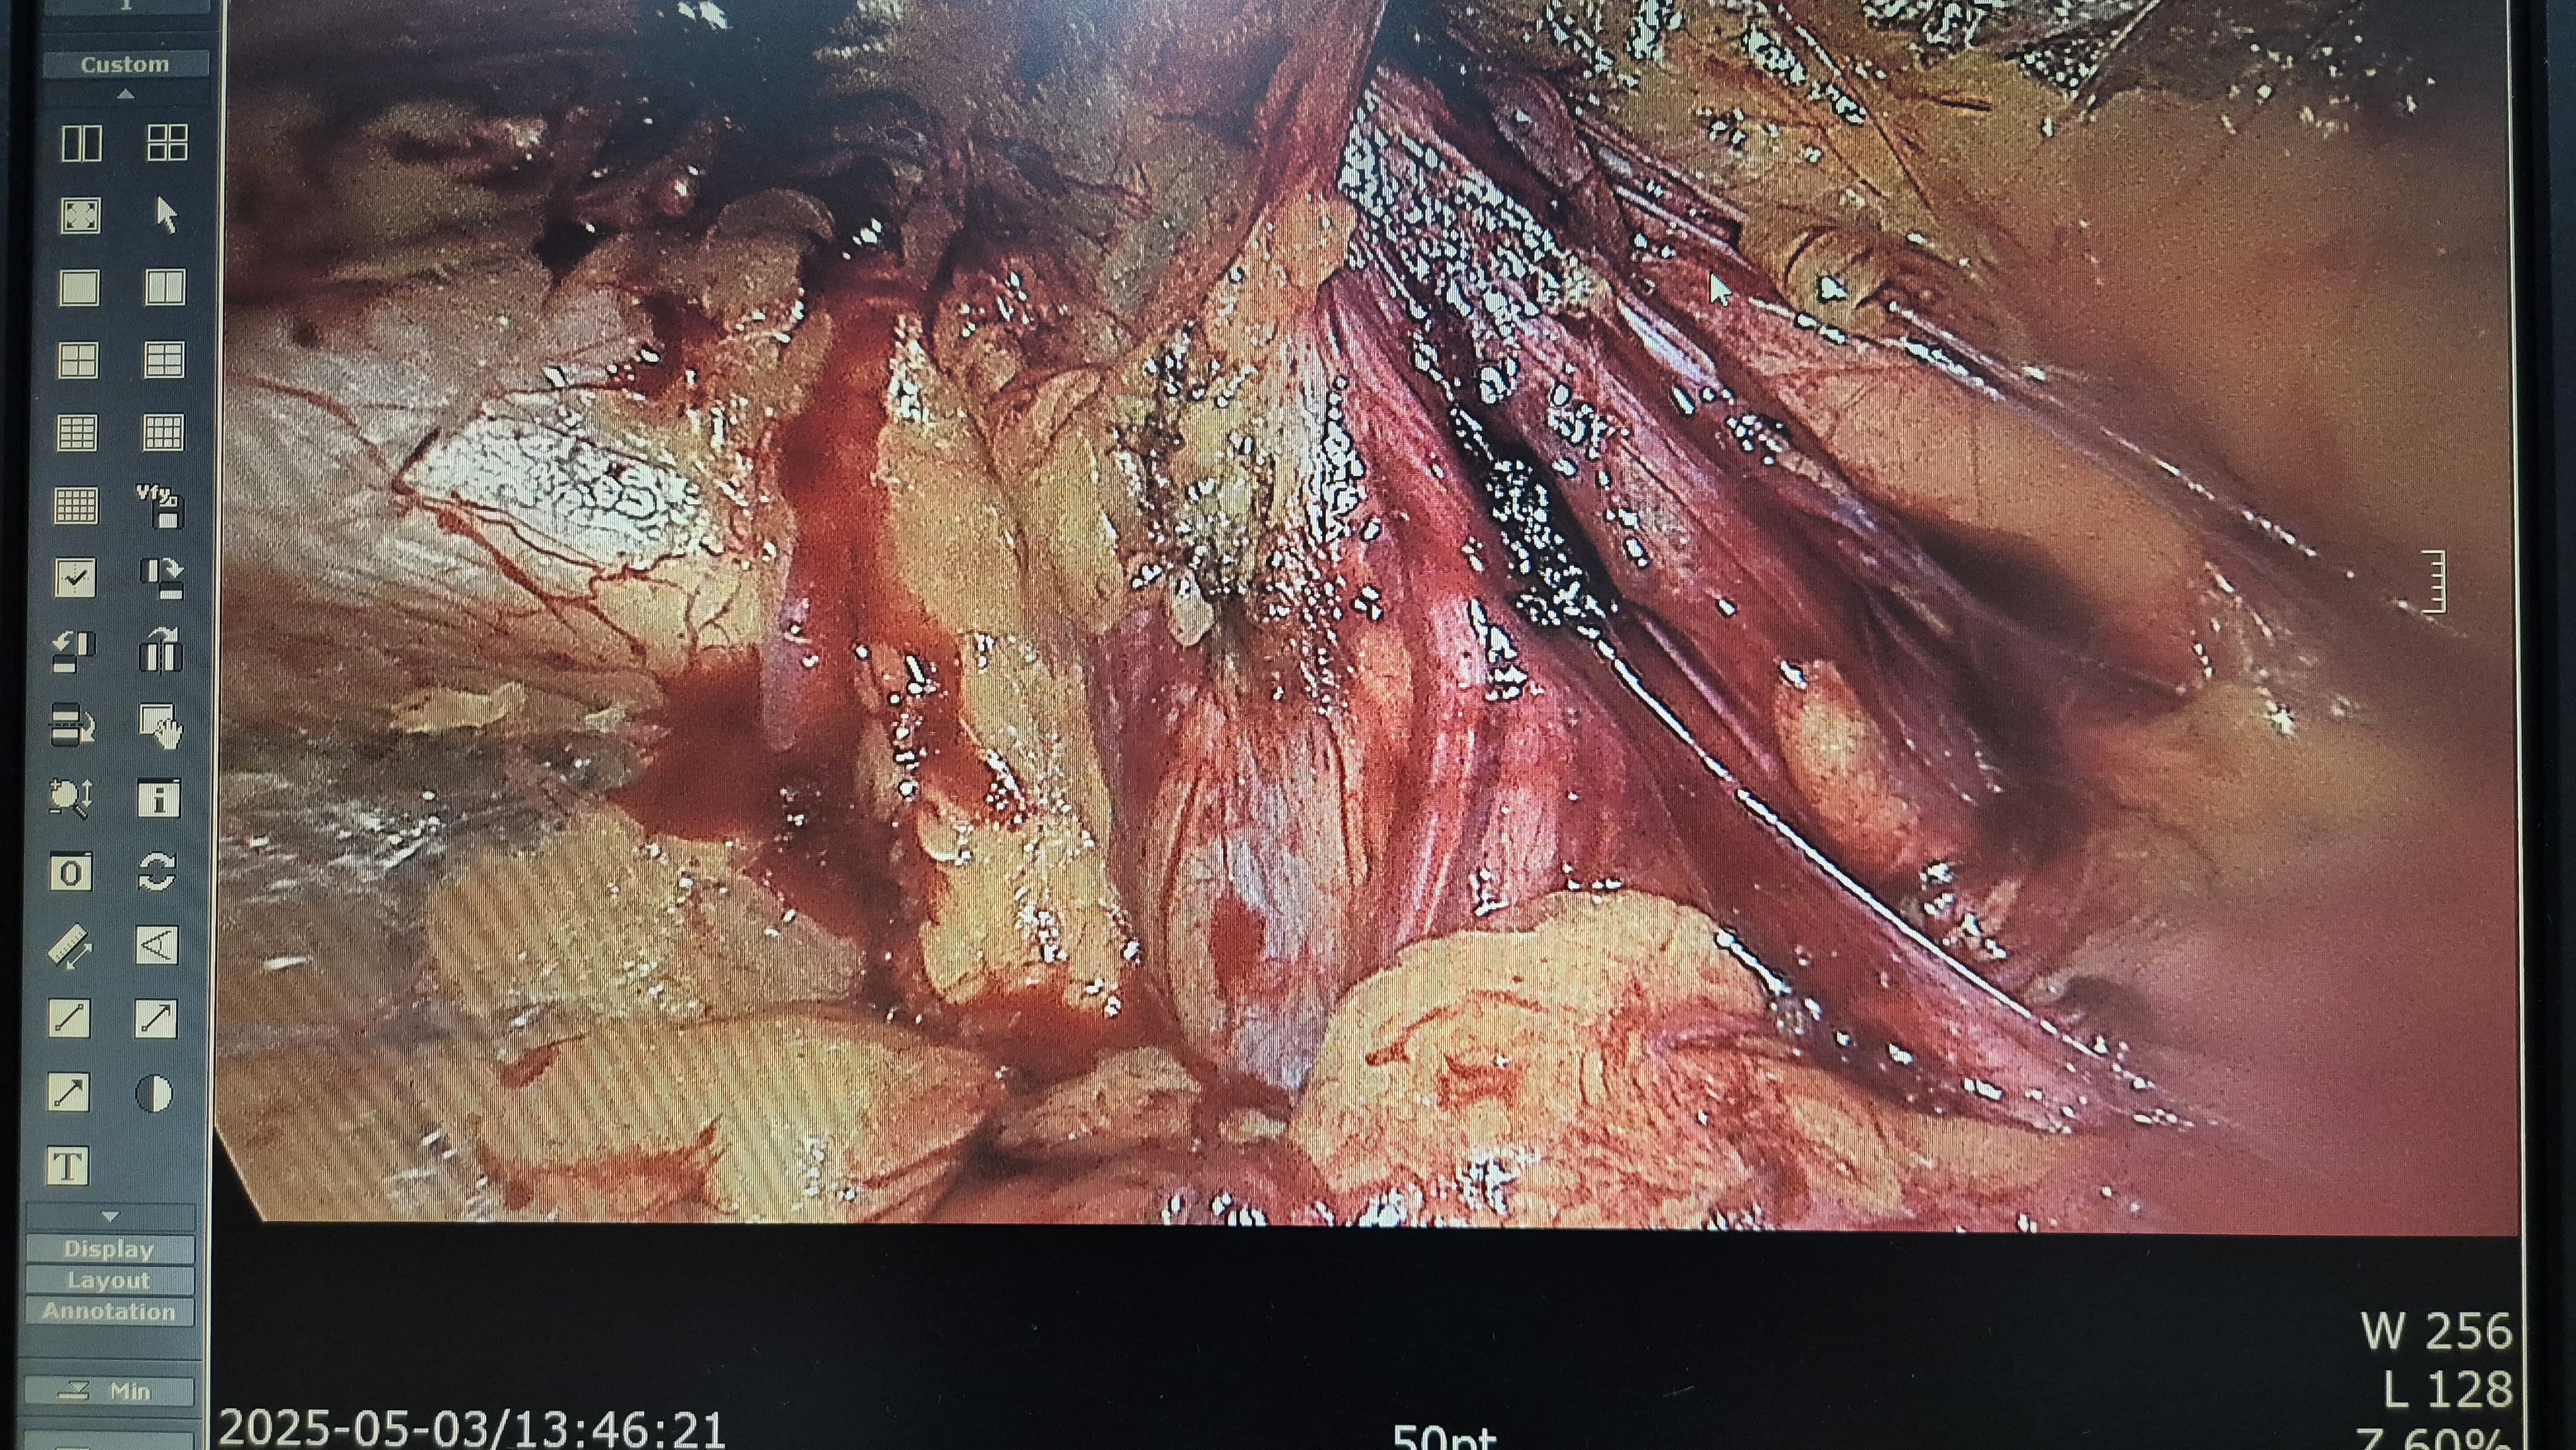

방금 복강경 탈장교정술을 시행했습니다.

탈장 획인후.

박리.

메쉬로 보강.